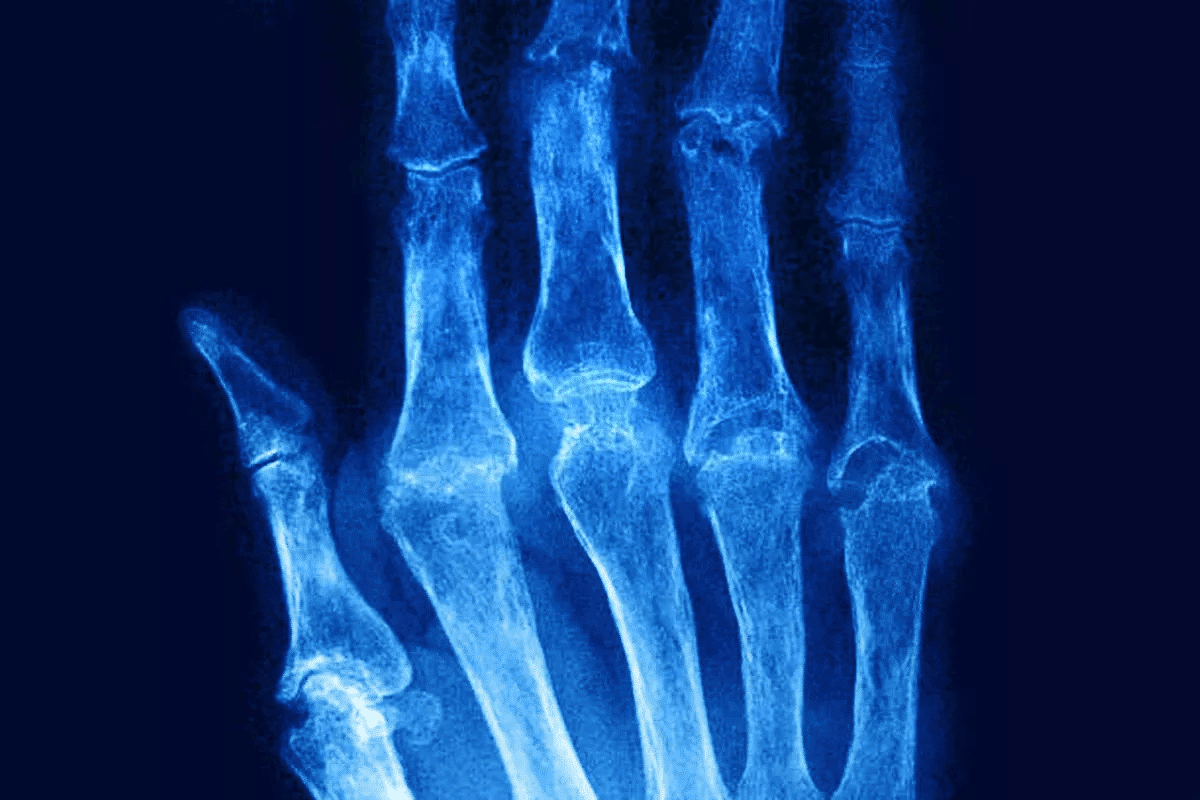

Stage 3: Severe Symptoms and Cartilage Damage

In stage three, RA really affects the joint. It causes cartilage damage and might lead to bone erosion. Symptoms get worse, with more pain, swelling, and less function.

If not treated well, the damage can’t be fixed. This can lead to big disabilities.

Stage 4: End-Stage Joint Destruction

The last stage of RA is when the joint is badly damaged. This can cause a lot of pain and make it hard to move. Treatment at this stage might include surgery to fix or replace the joints.

Joint Deformities and Functional Limitations

Advanced RA can lead to joint deformities that make moving hard. These problems come from long-term inflammation and damage to joints and surrounding tissues. Some common issues include:

- Ulnar deviation, where the fingers drift towards the ulna

- Swan neck deformity, characterized by hyperextension of the proximal interphalangeal joint

- Boutonniere deformity, involving flexion of the proximal interphalangeal joint

These issues not only hurt but also make everyday tasks hard. This leads to big problems with daily life and a lower quality of life.